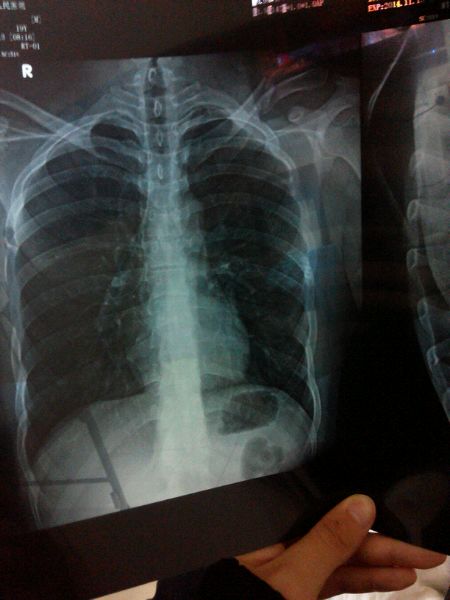

左肩锁骨粉碎性骨折 今天早上刚做完手术 打了钢板 痛死了

今天上午做了手术 打了钢板